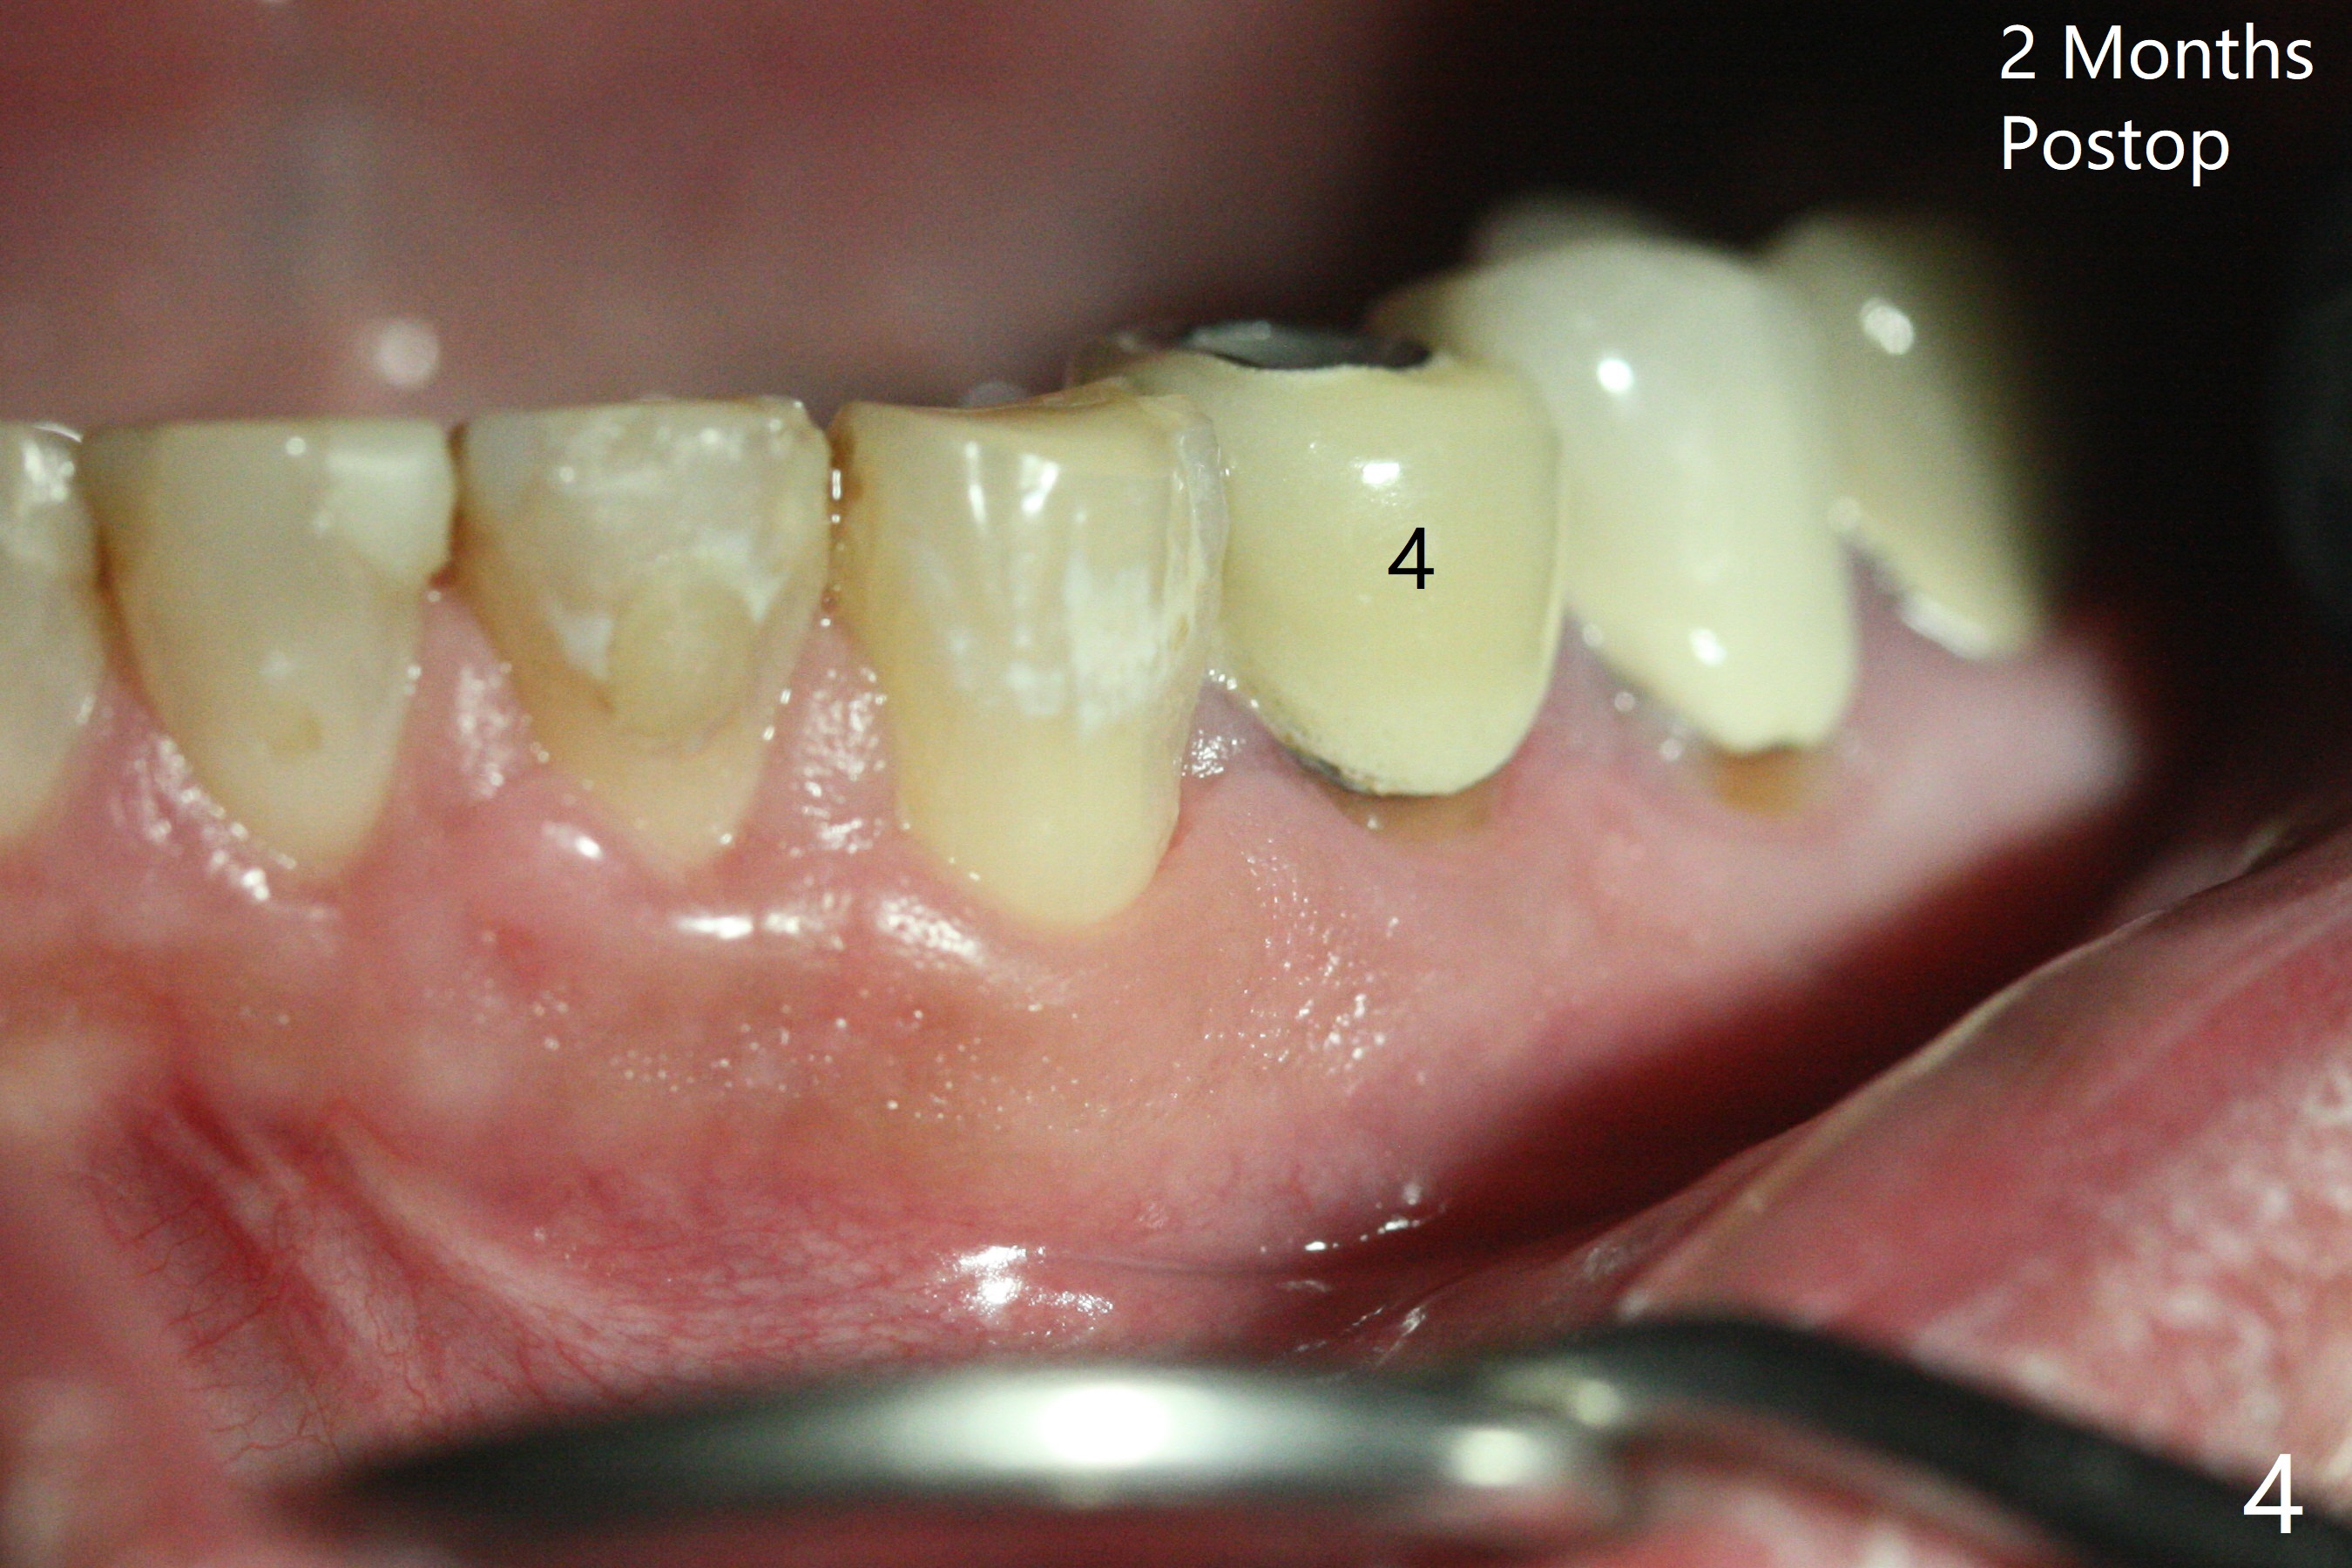

术前冷和电牙髓活力测定显示左下3活髓,不得不做一个长切口和附加切口(图二:>),在暴露颏神经后,在4根尖做囊肿切除术(图一),好像上颌窦外提升,使用上颌窦提升术器械才把囊肿挖出来,不同之处是颊侧骨壁特别厚,为了容易去除4根尖舌侧囊肿,做了根切(图三:<,与图三 ' (术前)对比),但是没做倒充,觉得根管充填完整。并且填入不少粘性骨块(图三)。病理报告:Left Mandibular Body, #21, Excisional Biopsy: Benign fibrous and granulation tissue with acute and chronic inflammation, consistent with periapical granuloma. Negative for odontogenic keratocyst and unicystic ameloblastoma. 左下颌骨体部,21号牙,切除性活检:良性纤维和肉芽组织伴有急性和慢性炎症,与根尖周围肉芽肿一致。牙源性角化囊肿和单房性造釉细胞阴性。术后两个月伤口愈合(图四),骨粉好像安居乐业(图五:*)。